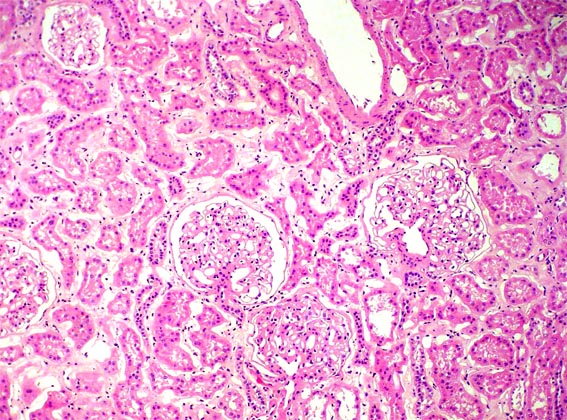

Figura 1.

H&E, X100.